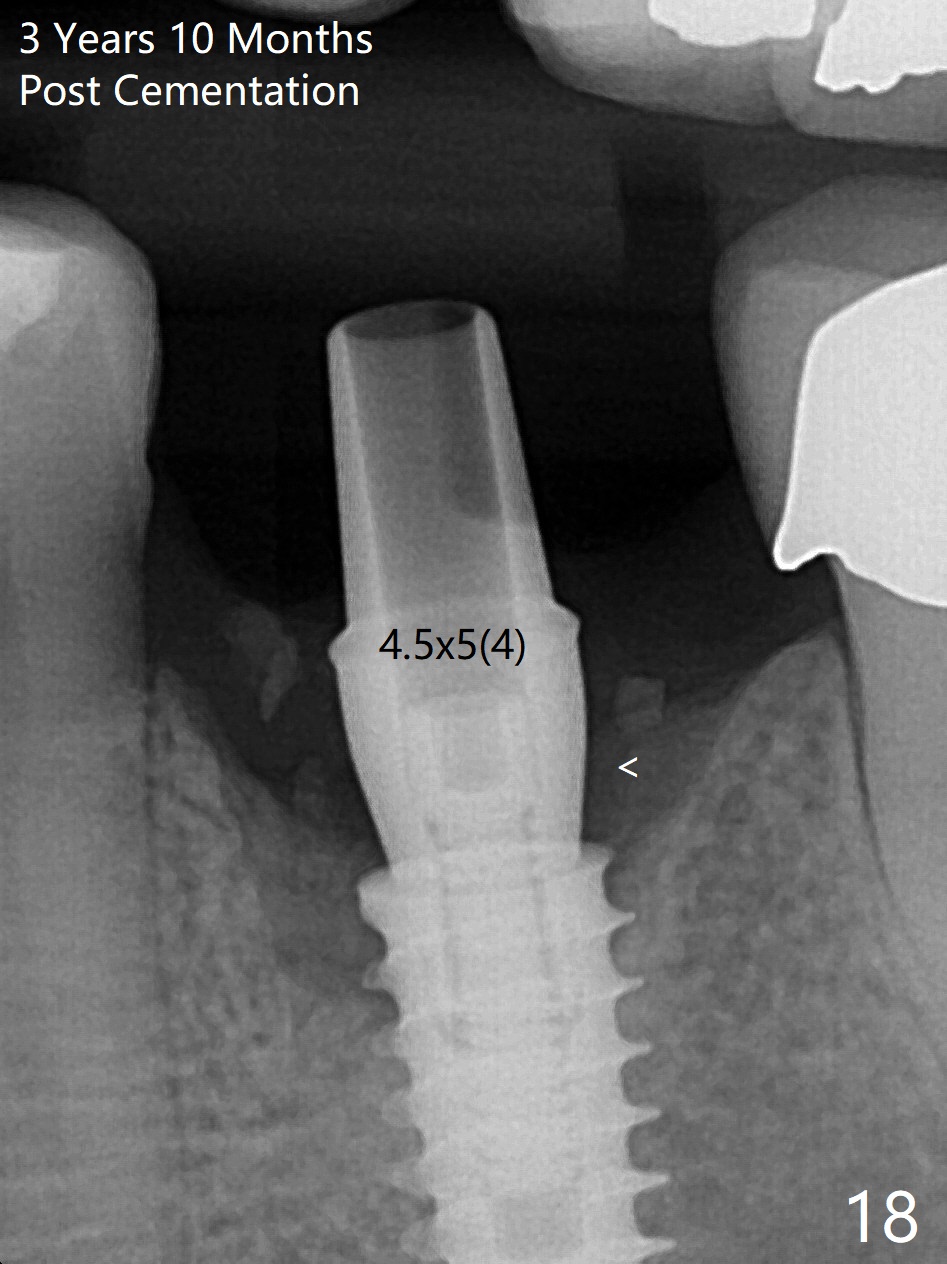

The gingiva looks healthy 8 months postop (3 months post cementation (after abutment screw retightening and addition of porcelain to proximal surfaces, Fig.12).  New bone has apparently covered the implant plateau (Fig.13 arrows). Bone density between threads increases 9 months post cementation (Fig.14).  There is 2 mm bone superior to the implant plateau mesial and distal 1 year 9 months post cementation (Fig.15,16).  The crown/abutment is loose 3 times (3 months (Fig.14), 11 months (between Fig.14 and 15) and 2 years 3 months post cementation).  In spite of being stable 3 years 10 months post cementation, a smaller abutment is placed (Fig.17 (PA), 18 (BW)) with impression for a new crown.  After intraoral cementation, the new crown/abutment is removed for residual cement removal.  When the complex is reseated, it is not smooth, probably due to proximal undercut.  Fortunately the abutment appears to be completely seated, followed by 20 Ncm torque (Fig.19).